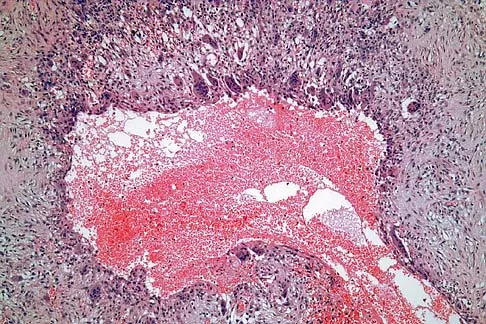

A 69-year-old man has a painful slow-growing lesion of the distal phalanx of his thumb. History reveals that he has had chronic osteomyelitis of the thumb for the past 12 years. The radiograph and biopsy specimens are seen in Figures 9a through 9c. Treatment should consist of

The diagnosis is squamous cell carcinoma. The radiograph shows a destructive lesion, and the histologic slides demonstrate squamous cells invading bone. The preferred treatment for squamous cell carcinoma is wide resection; however, in this location a wide margin can be achieved only with amputation. Overall survival in patients with squamous cell carcinoma secondary to chronic osteomyelitis is not significantly worse than that expected for age-matched controls. Dell PC: Hand, in Simon MA, Springfield D (eds): Surgery for Bone and Soft Tissue Tumors. Philadelphia, PA, Lippincott-Raven, 1998, pp 405-420.